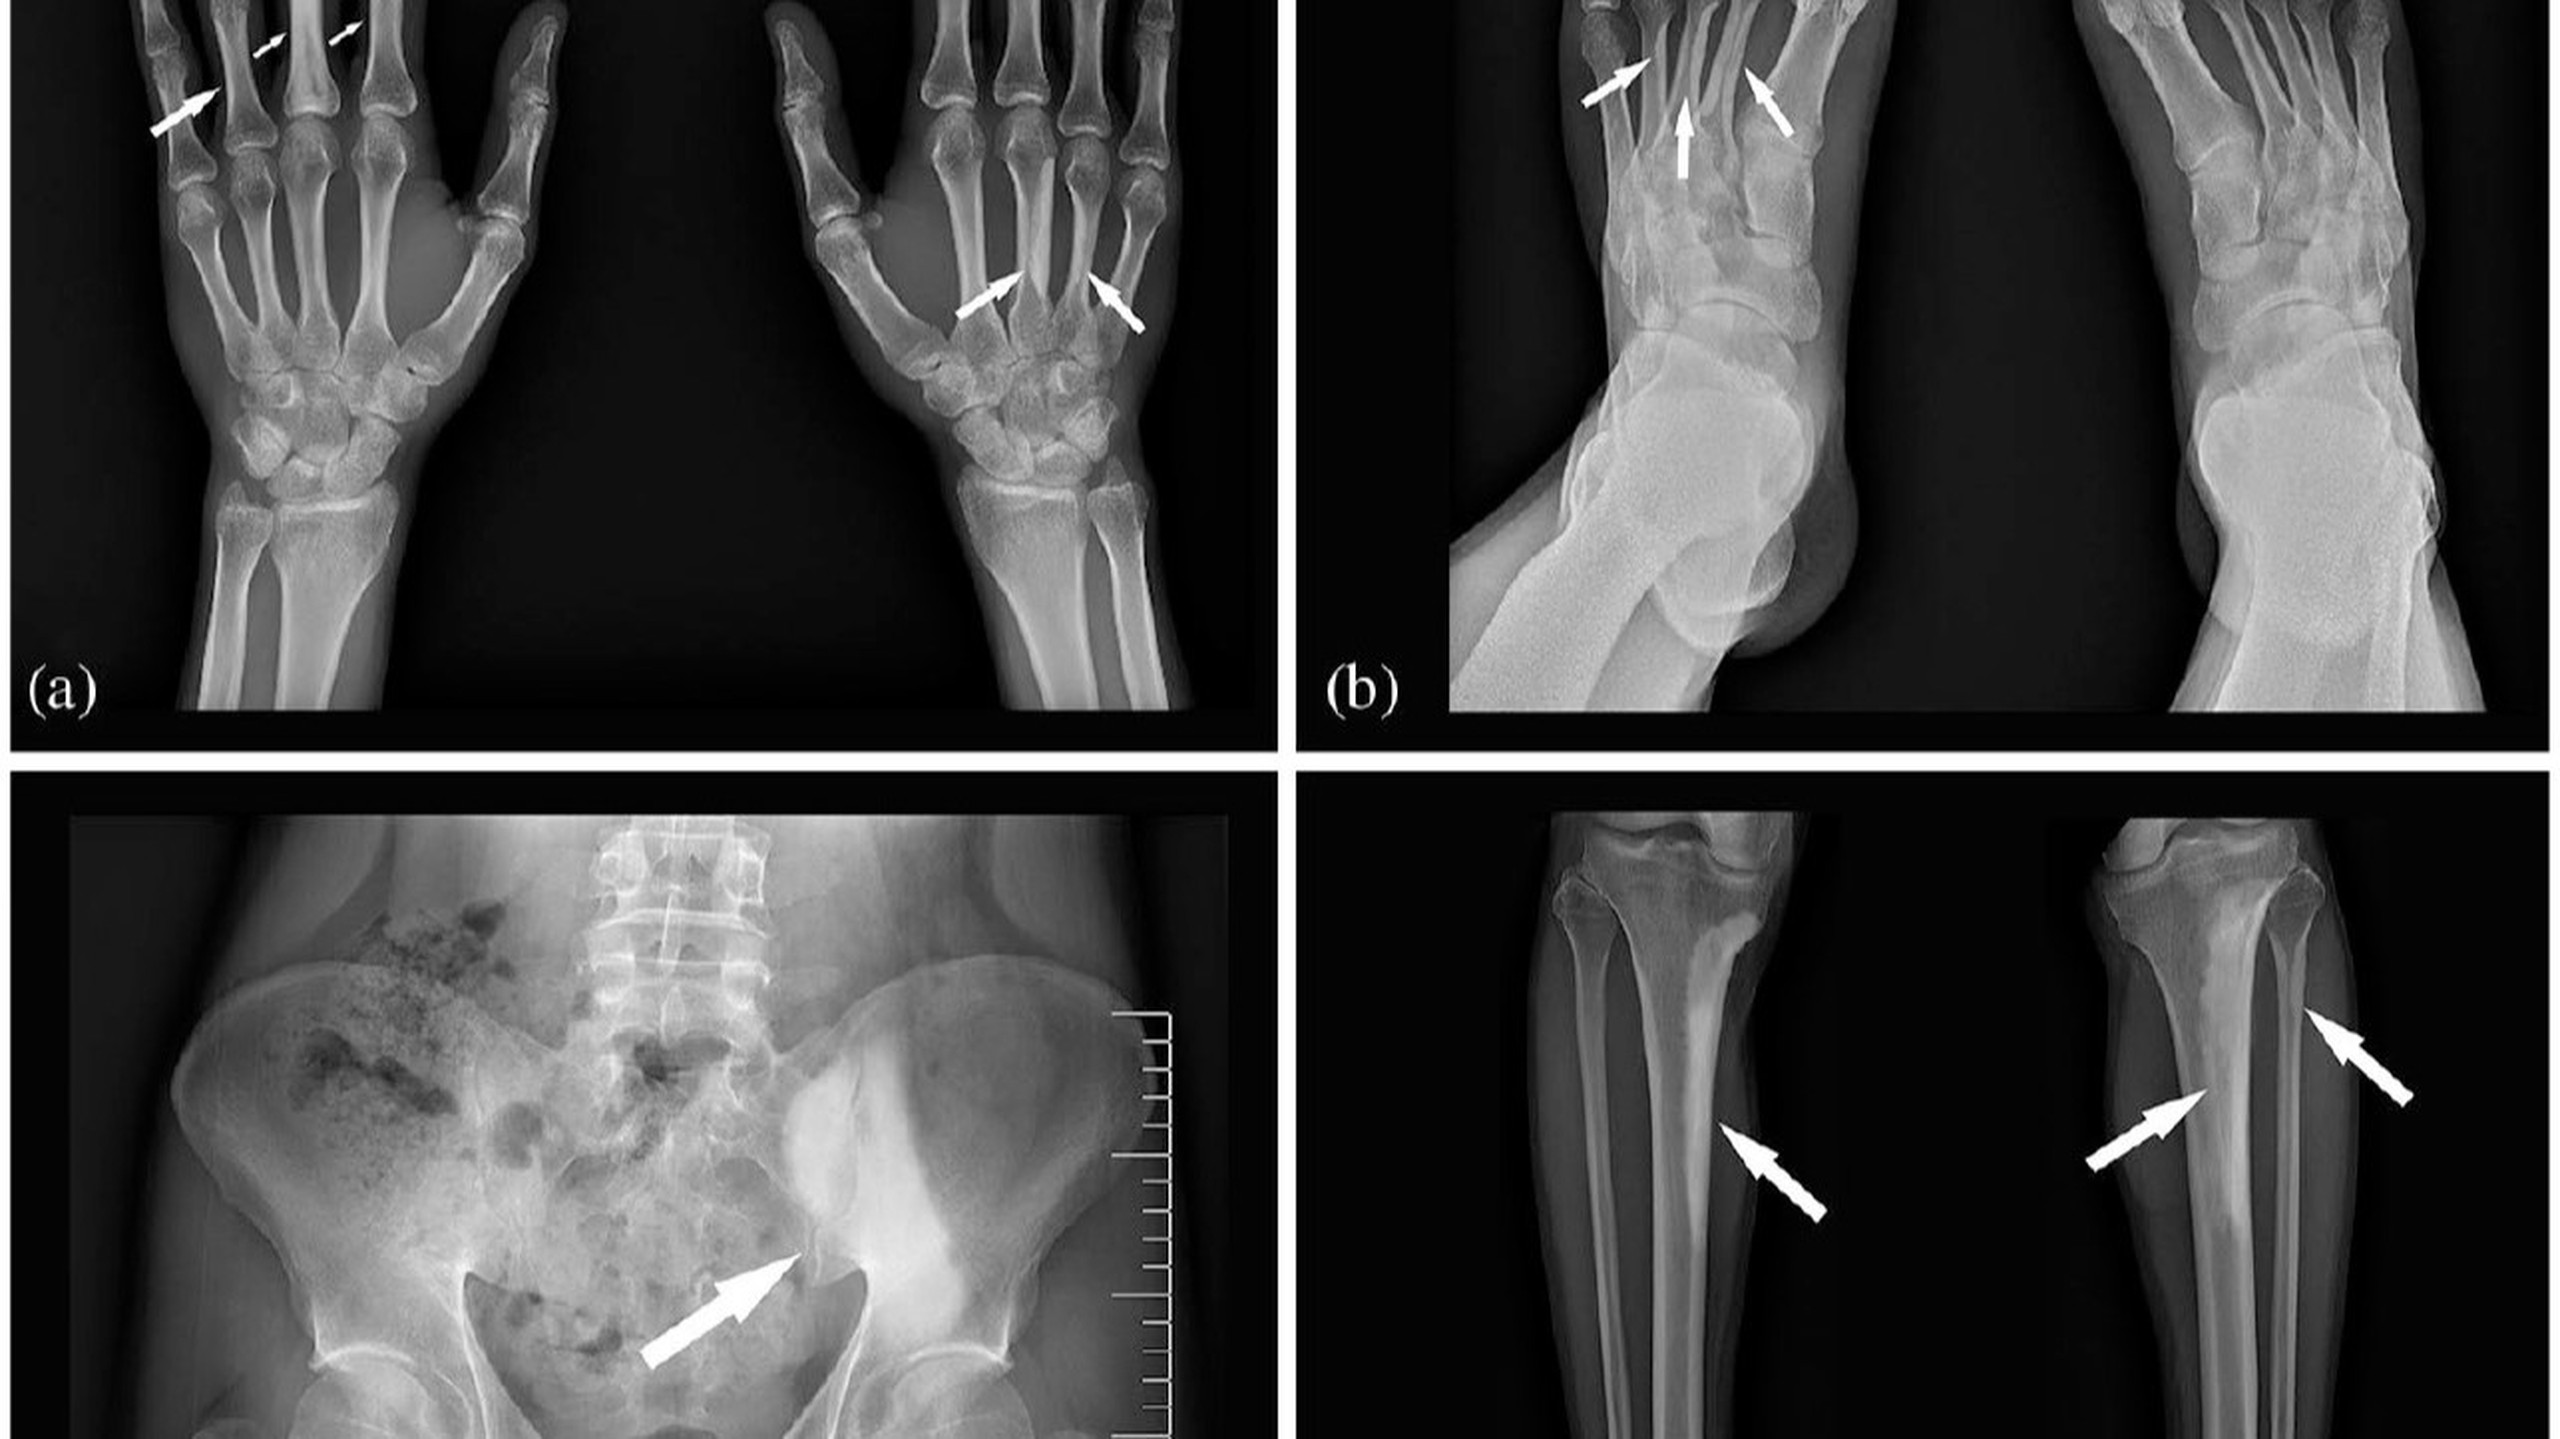

Bệnh nến xương (Melorheostosis) hay bệnh Leri lần đầu tiên được nhà thần kinh học người Pháp Andre Leri (1875-1930) và J Joanny trình bài vào năm 1922. Tên gọi bắt nguồn từ tiếng Hy Lạp với “melos” nghĩa là chi và “rhein” nghĩa là chảy do bệnh lý này đặc trưng bởi hình ảnh tăng sinh xương nhìn như kiểu nến chảy trên phim x-quang.

Ở trẻ em thường không có triệu chứng, bệnh chỉ được chẩn đoán khi được phát hiện tình cờ trên x-quang với dấu hiệu “nến chảy”. Trong đó dấu hiệu “nến chảy” là hình ảnh phì đại vỏ xương không đồng đều, thường xảy ra ở một phía của xương bị tổn thương, giống như hình ảnh nến chảy một bên của đèn cầy.

Chẩn đoán được thực hiện trên phim chụp X-quang với hình ảnh "sáp nến chảy nhỏ giọt" cùng tình trạng tăng sinh xương dày đặc chạy dọc theo vỏ xương.